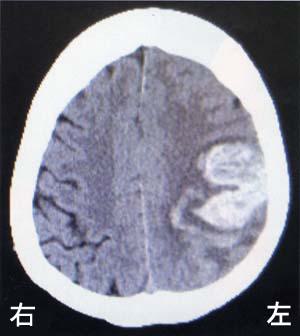

42 歳の男性。右利き。自営業。 3 年前に脳出血発症後、回復期リハビリテーション病院を経て自宅退院し復職したが、仕事中に再発した。初発時の頭部 CT と再発時の頭部 CT を別に示す。再発時の新たな症状として最も考えられるのはどれか。

1

昏睡

2

構音障害

3

右同名半盲

4

回転性めまい

5

Gerstmann 症候群